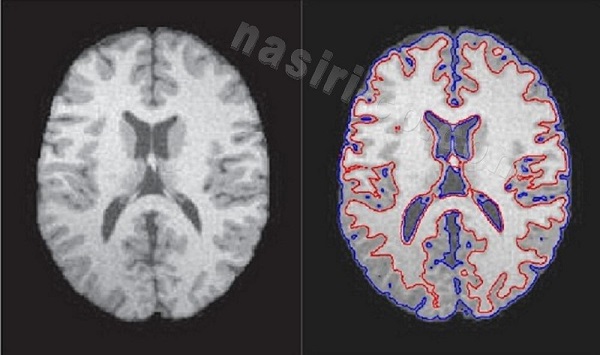

پردازش تصویر و تصاویر تشدید مغناطیسی(MRI) مغزی

ناحیه بندی به روش کانتور فعال

ناحيه بندي به هدف تشخيص بيماري ها و سرطان